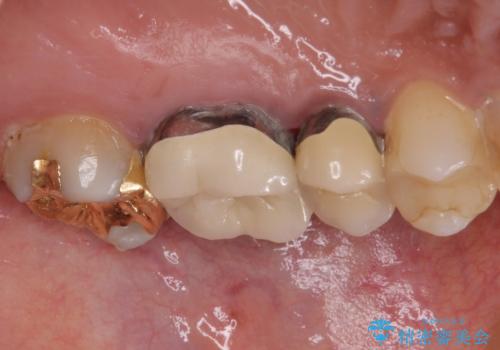

処置開始前から神経組織を部分的に除去する可能性が高いことが分かっていたため、ラバーダムなどの環境を整え、無菌的環境下にて処置を進めて行きました。

虫歯は深くまで進行しており、歯冠部の神経から出血が認められました。神経を部分的に除去したところ出血が治まったので、生体親和性の非常に高いセメントにて充填し、仮封をしました。